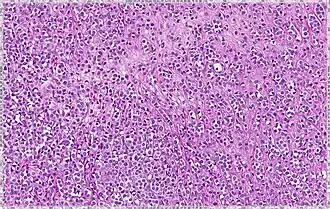

| Pleomorphic | Classical-appearing but with pleomorphic cells. It may include signet-ring cells, or plasmacytoid cells (pictured) which have abundant cytoplasm and eccentric nuclei. |  |